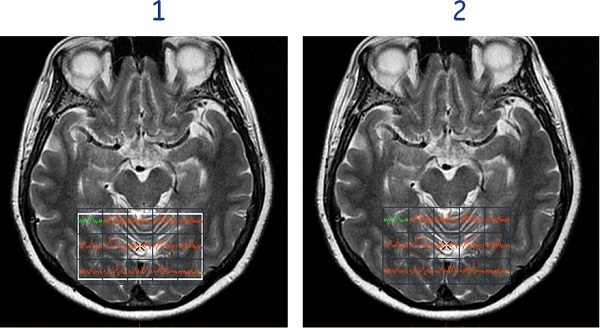

• Show/Hide Spectroscopy voxels toggles the spectrum within each voxel on and off.

Figure 9. Show Spectroscopy voxels (1), Hide Spectroscopy voxels (2)

• Show/Hide Structural View toggles the spectrum and the voxel numbering within each voxel on and off the image.

Figure 10. Show Structural View (1), Hide Structural view (2)